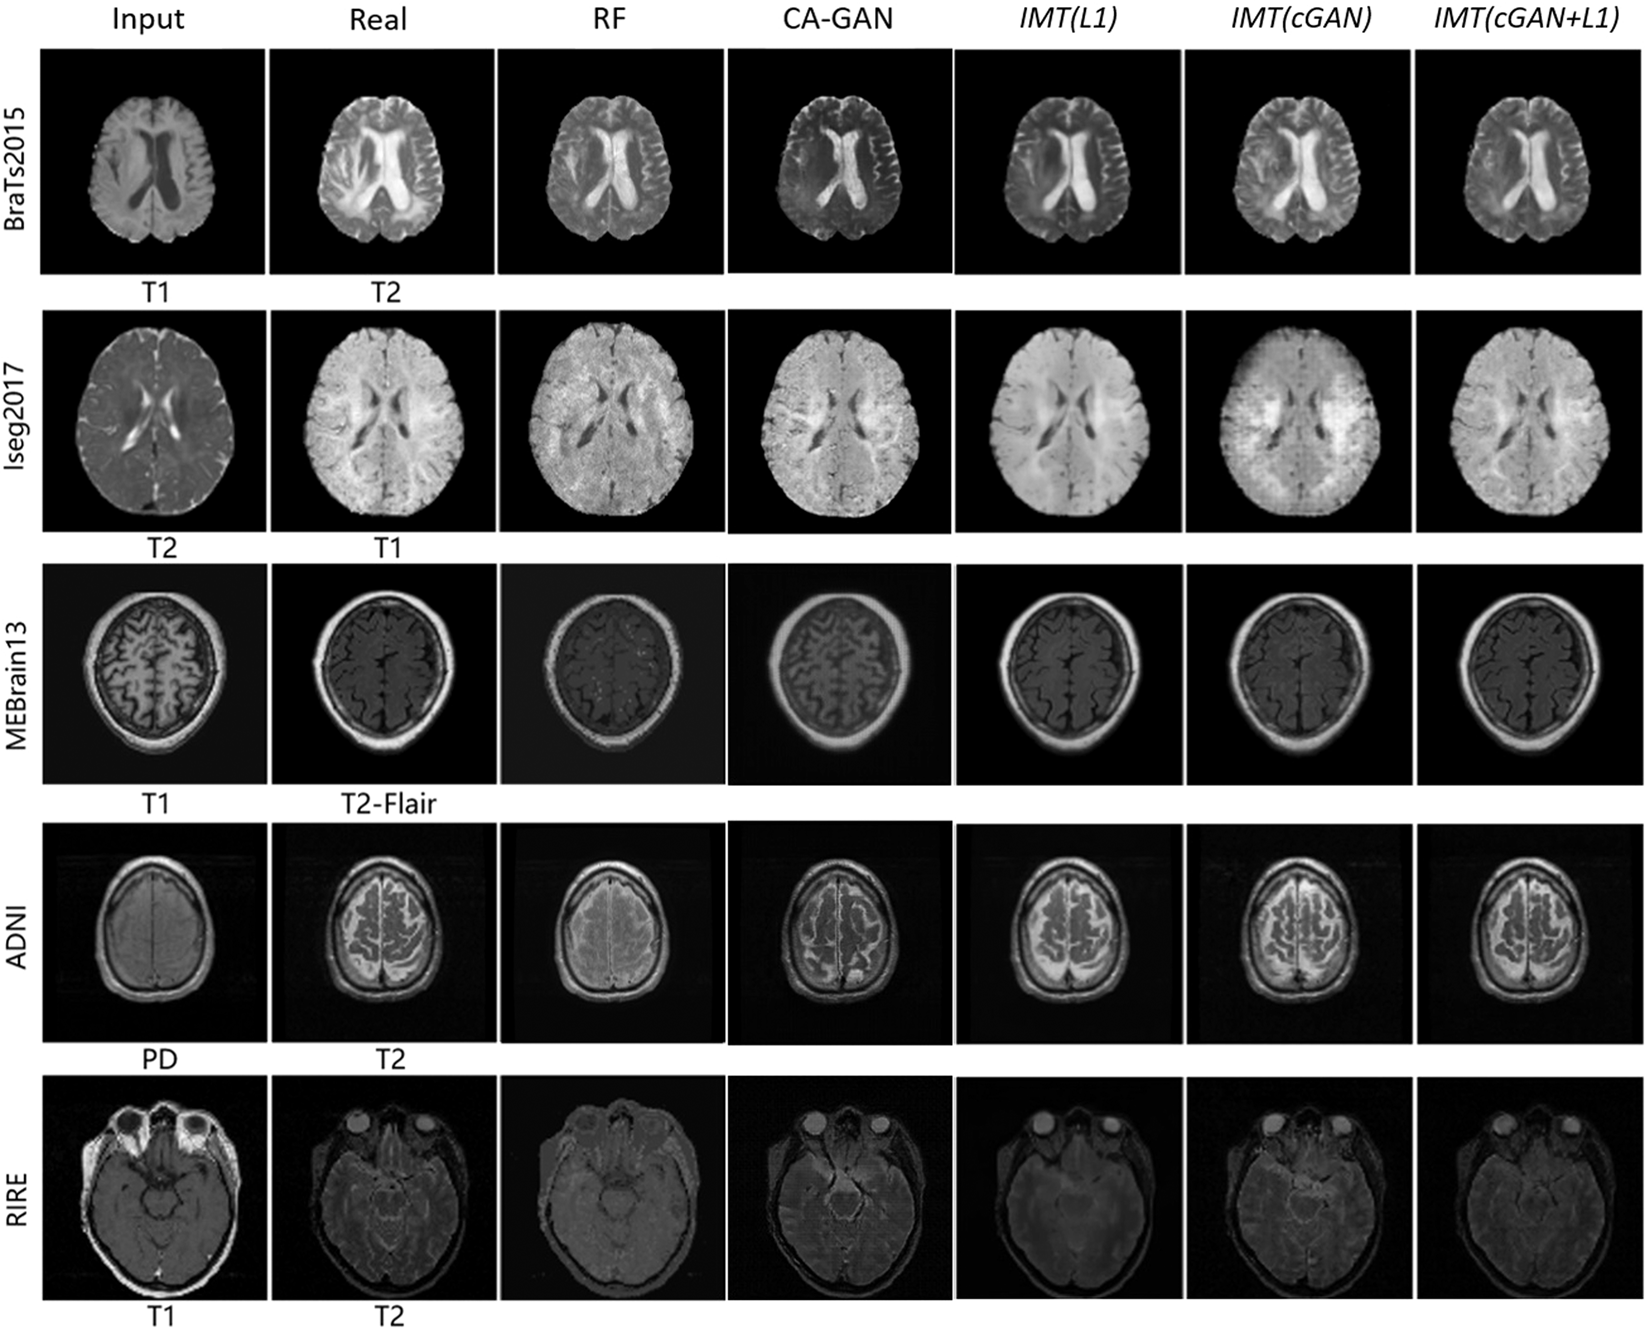

Figure 7

Samples of cross-modality generation results on five publicly available datasets including BraTs201560, Iseg201761, MRBrain1362, ADNI30, and RIRE63. Results are selected from top performing examples (relatively low MAE, high PSNR, high MI, and high PSNR collectively) with four approaches. The right five columns show results of the random-forests-based method (RF)5, the Context-Aware GAN (CA-GAN)30 and IMT framework with different loss functions (L1, cGAN, cGAN + L1).